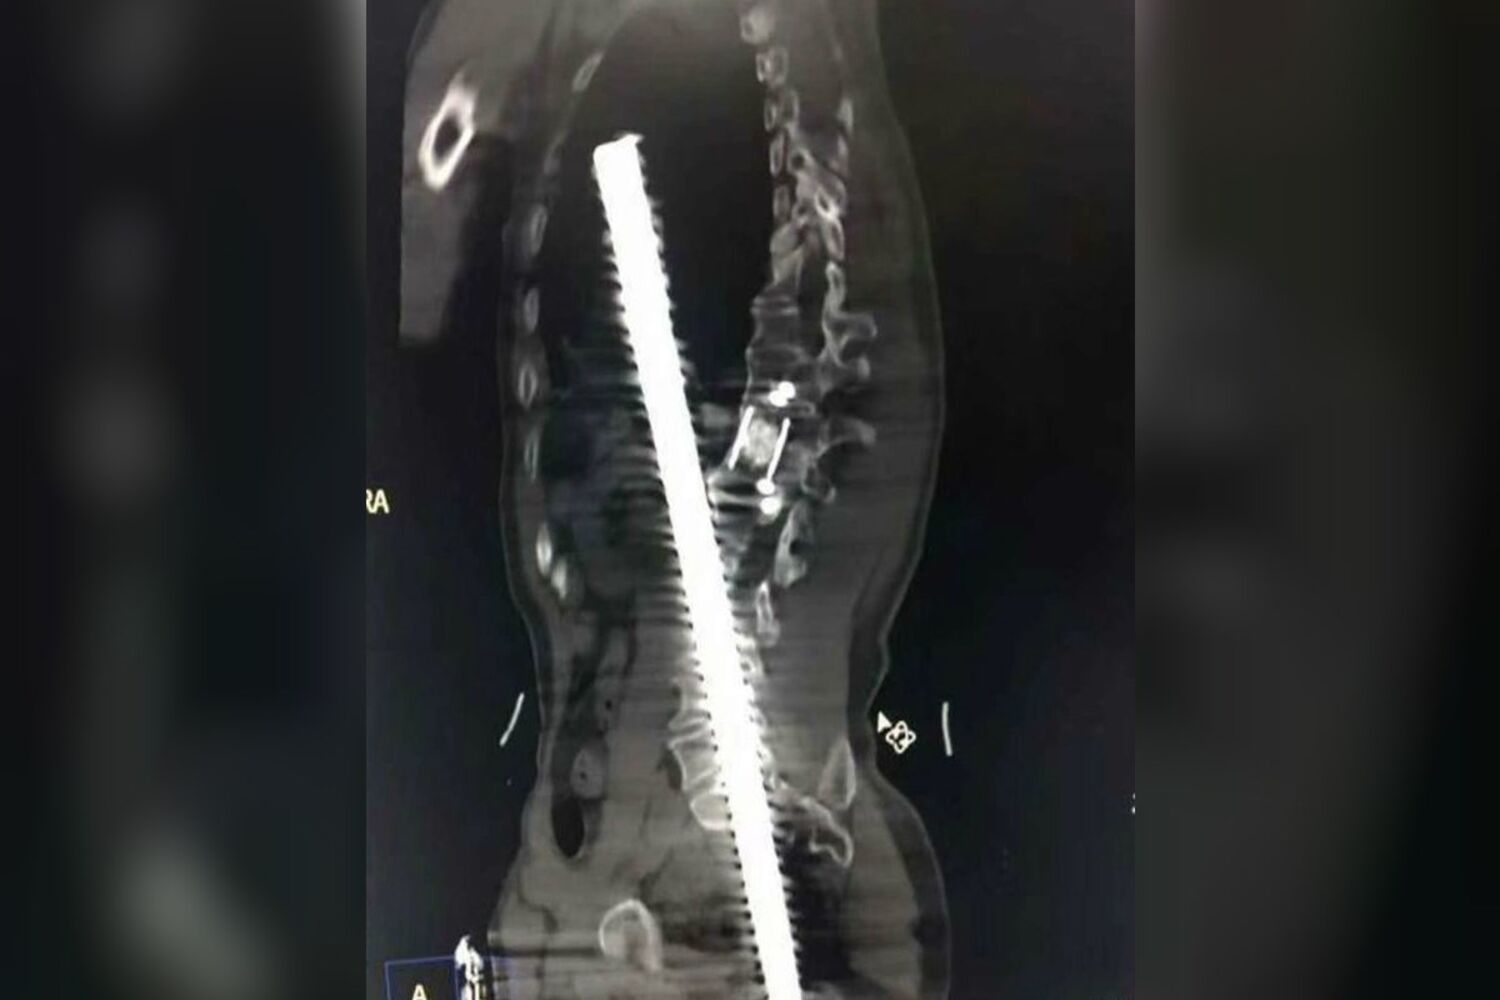

As radiografias mostram a gravidade das lesões. O homem empalado foi operado de urgência e conseguiu sobreviver, dado que, com muita sorte, a barra não atingiu nenhum órgão vital.

O médico que o operou, Zhang Jianwen, revelou que cerca de 61 cm dos 80 cm da barra de aço reforçado entraram no corpo do operário. Os bombeiros tiveram de cortar a barra de aço para levar o homem para o hospital, onde foi submetido a uma operação de seis horas.